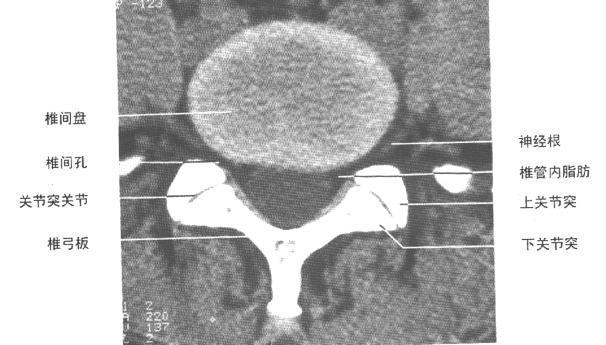

以前很少注意上下关节突